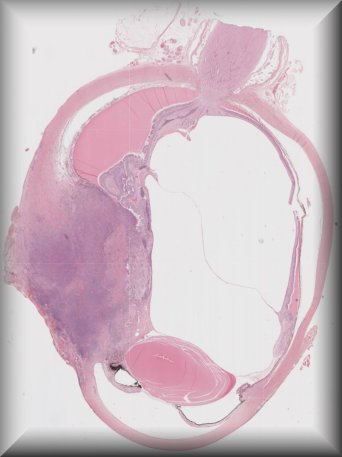

Thomas J. Cummings (Durham, North Carolina): 54-year-old male with multiple systemic infections underwent enucleation after 2 months of pain, redness and acute loss of vision. |